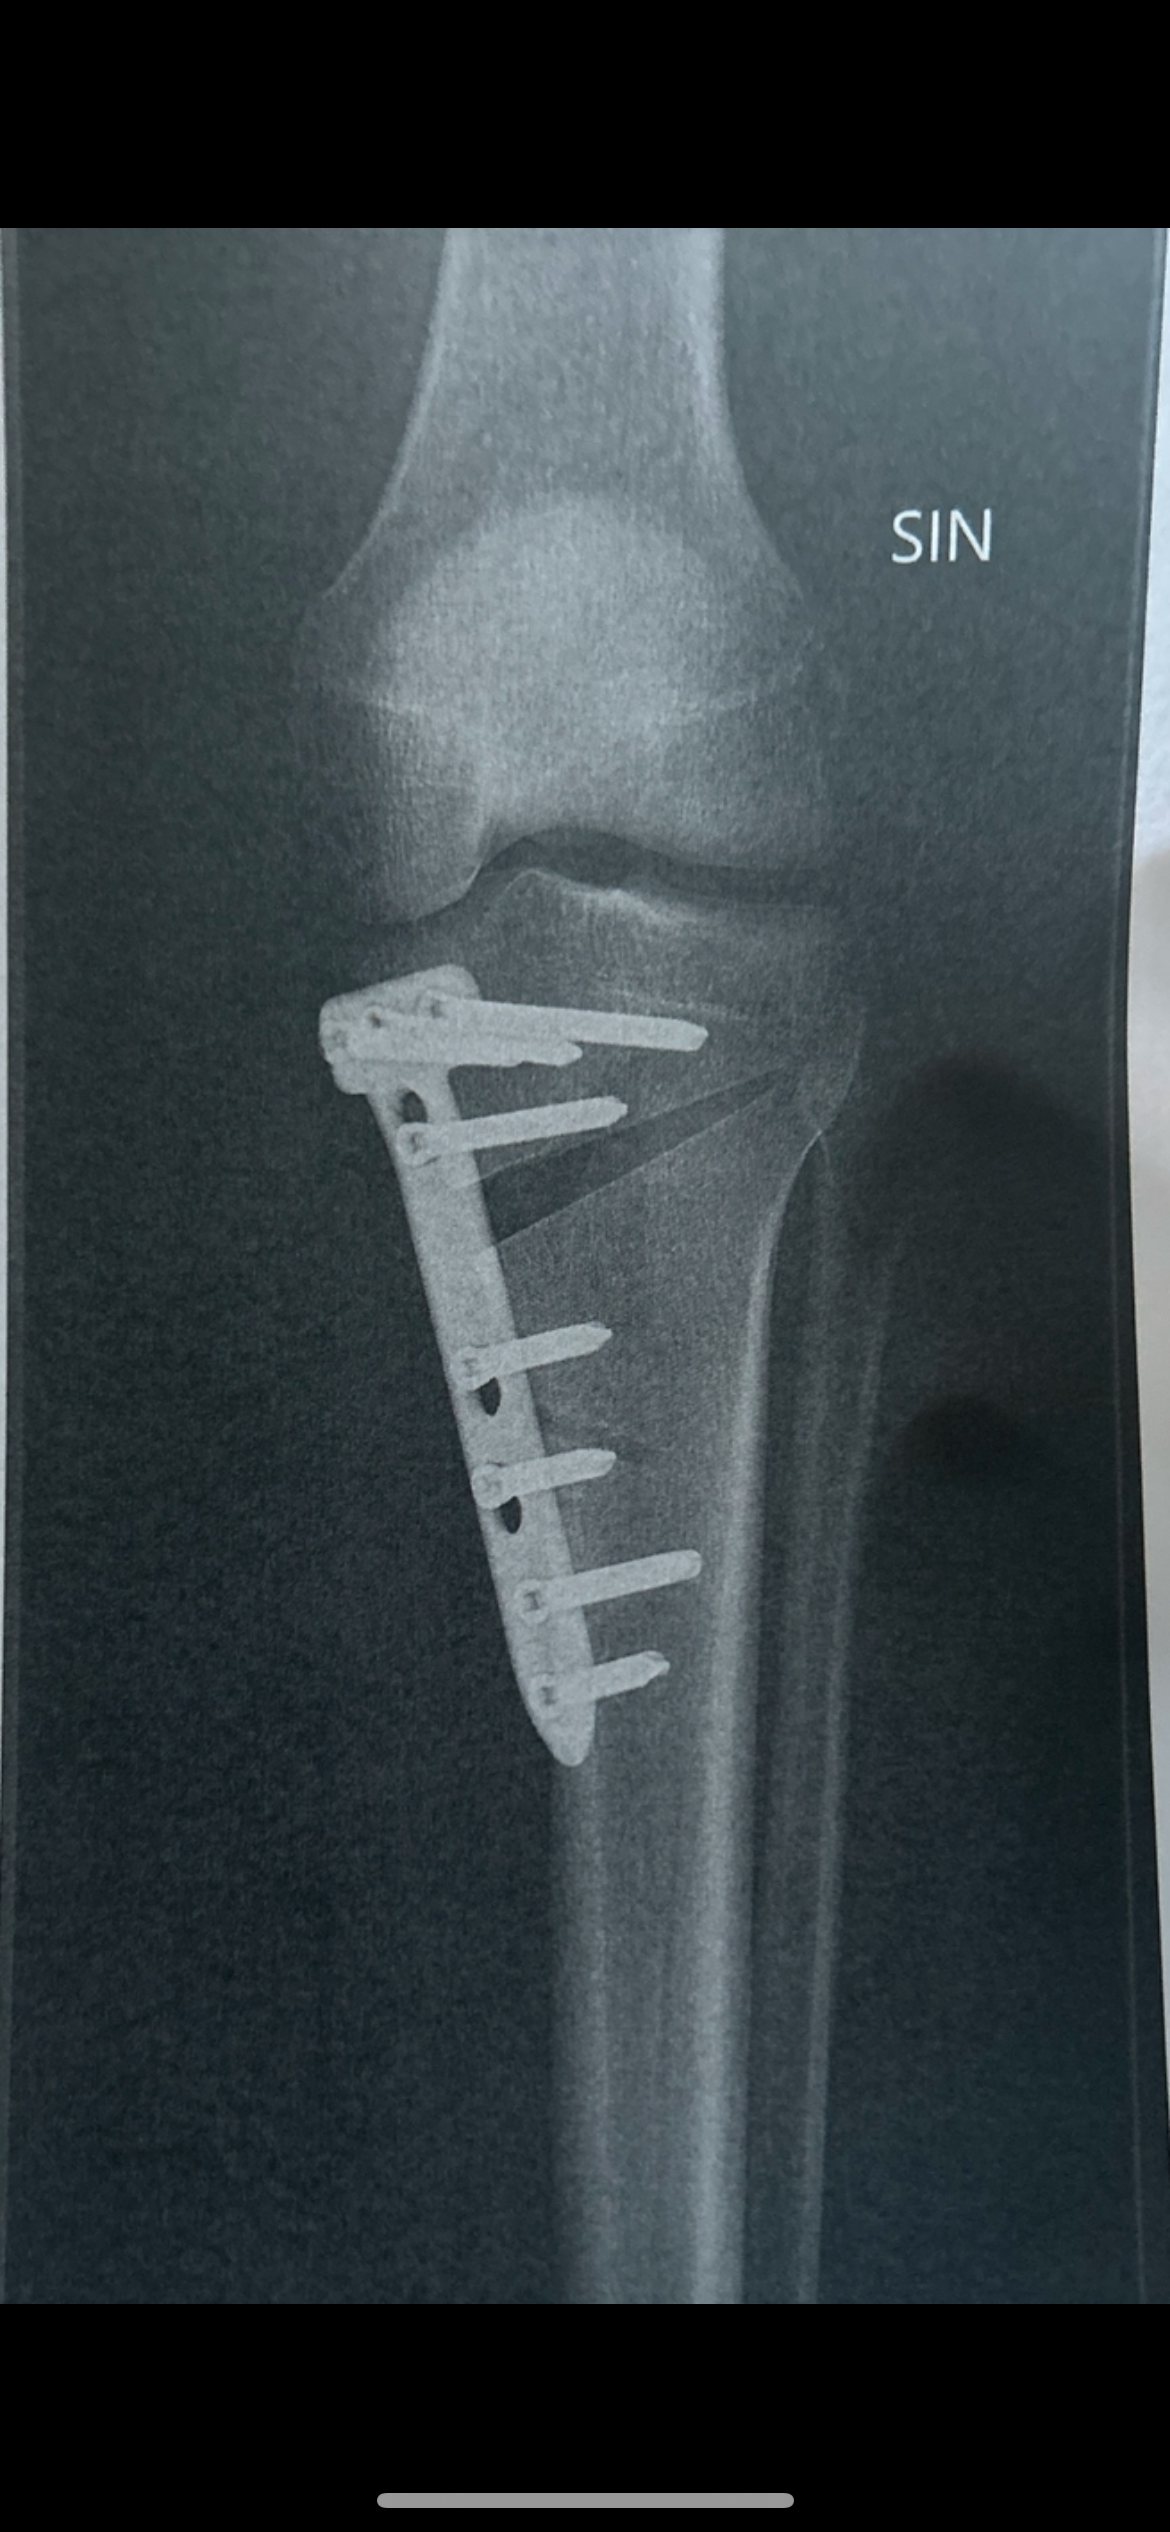

They cut a 1gap in my leg and it seems logical that i have to eat more right? Because my body needs energy to refill that gap with bone? Or maybe i just beed more nutrients? Its just a general question but i mean it seems logical that you have to eat more to make the body fill in the bone quicker and better. What do yall think?

Heres an x ray for refference: